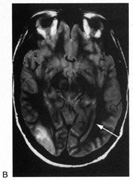

OPTIC TRACTS The optic tract is the continuation of the anterior visual system from the optic chiasm to the LGN. Only the contralateral hemifield is represented. The decussated nasal retinal fibers are not initially well aligned topographically with the other eye's temporal retinal fibers, but retinal correspondence improves towards the termination of the tract at the lateral geniculate nucleus (LGN). The retinotopic map is also tilted in the optic tracts, so that the macula is represented dorsally, inferior retina (superior visual field) laterally, and superior retina (inferior visual field) medially (see Chapter 4, Fig. 9).1 The magnocellular and parvocellular axons also may be segregated, with magnocellular axons more ventral.2 Both of these topographies are mirrored in the LGN. The main vascular supply of the optic tract is the anterior choroidal artery. The functional anatomy of the optic tract is reflected in several important clinical findings. First, partial lesions cause contralateral homonymous defects that can be markedly incongruous (different patterns of visual loss in the two eyes) because of the poor topographic alignment of the two retinal maps (Figs. 1 and 2).3,4 In contrast, lesions of the optic radiations cause only mild incongruity and striate lesions are highly congruous. Complete transection of the optic tract leads to congruous complete hemianopia, although this is less frequent than partial lesions. Reduced acuity with an optic tract lesion indicates bilateral tract damage or extension of the lesion to the optic chiasm or optic nerves.4,5 Second, because the axons in the optic tract originate from retinal ganglion cells, damage to the tract causes optic atrophy over time. This is present in both eyes, but because only half or less of the axons of each eye are affected, the atrophy is less severe than with most optic neuropathies. Also, the pattern of optic atrophy differs between the eyes. In the eye with temporal field loss, the axons from the nasal retina are affected. The fibers from the nasal periphery enter the nasal side of the disc, whereas those from the nasal macula enter the temporal disc in the papillomacular bundle. Atrophy is seen in these nasal and temporal wedges of the disc but the superior and inferior sectors are spared, because these contain fibers from the temporal retina. The result is “bow-tie” optic atrophy (see Fig. 1). In contrast, atrophy in the eye with nasal field loss affects the superior and inferior wedges and papillomacular bundle, but not the nasal wedge. This appears as diffuse or temporal disc pallor. Another distinctive optic disc picture occurs in the eye with temporal field loss when a mass lesion causes papilledema and compresses the optic tract. Disc swelling occurs in the superior and temporal disc but not in the atrophic bow-tie regions, creating “twin-peaks” papilledema (see Fig. 2).6,7 Third, because fibers for the pupillary reflex also travel in the optic tract, often there is a relative afferent pupillary defect (RAPD). With a significantly incongruous hemianopia, the RAPD may be in the eye with greater visual loss. With a complete tract lesion the RAPD is in the eye with temporal field loss,4,8 because the temporal hemifield is larger and there are slightly more axons from the nasal than temporal retina (ratio 53:47). The RAPD is a useful sign in optic tract hemianopia because it may be present at a time when optic atrophy has not yet developed (see Chapter 15).9 Other reported pupillary abnormalities include Wernicke's hemianopic pupil, which is an intraocular afferent pupil defect, with less pupillary constriction from light on the hemianopic hemiretina compared to light on the intact hemiretina. Wernicke's hemianopic pupil is difficult to elicit at the bedside because of intraocular light scatter,3 although it may be seen with computerized pupillometry (Fig. 3). The combination of optic atrophy, RAPD and field incongruity is important to recognize with homonymous hemifield defects, because it changes the differential diagnosis of hemianopia (Fig. 14). Most hemifield defects from lesions of striate cortex or the optic radiations result from vascular disease or other intracerebral pathology. Most optic tract lesions are compressive extrinsic masses, with a differential diagnosis similar to that for optic chiasmal lesions (see Chapter 6). In fact, patients with combined damage to the optic tracts, chiasm, and nerve are not rare.4,10–13 Pituitary adenomas, giant aneurysms of the internal carotid artery, meningiomas, and craniopharyngiomas are the chief causes of optic tract dysfunction. The investigation of choice is imaging of the parasellar region, with coronal and axial sections and contrast administration. Less common lesions include inflammatory conditions such as multiple sclerosis3,11,14,15 and sarcoidosis (see Fig. 1).16 Intrinsic optic pathway gliomas may occur in the optic tracts. Vascular lesions are rare, but there are reports of cavernous angiomata10,17 or arteriovenous malformations.18 Optic tract infarction can complicate anterior temporal lobectomy, possibly from vasospasm of the anterior choroidal artery.19 Trauma can affect the optic tract.3 Radiotherapy of pituitary tumors may be followed years later by optic tract necrosis.13 Optic tract dysfunction is a side effect of alpha-interferon.20 On occasion there is congenital absence of the optic tract 21; such patients are often unaware of their hemianopia. Associated abnormalities are unusual.3 These include endocrine disturbances from hypothalamic dysfunction and memory impairment from temporal lobe involvement,22 reflecting the proximity of the optic tracts to these structures (see Chapter 4). LATERAL GENICULATE NUCLEUS The LGN is a subnucleus in the ventro-postero-lateral corner of the thalamus. Neighboring thalamic subnuclei include the medial geniculate nucleus ventromedially, ventral posterior nucleus dorsomedially, and pulvinar superiorly and dorsally. The medial geniculate nucleus gives rise to the acoustic radiations, which pass by the dorsomedial aspect of the LGN on their way to the auditory cortex in the temporal lobe. The optic radiations arise from the dorsolateral surface of the LGN. Ventrally, the hippocampus and parahippocampal gyrus face the LGN across the ambient cistern and the inferior horn of the lateral ventricle. The LGN has a dual blood supply: the anterior choroidal artery, a branch of the internal carotid artery, and the lateral choroidal artery, a branch of the posterior cerebral artery. The anatomy of the vascular territories within the LGN has been debated. Initial studies suggested that the anterior choroidal artery supplied the medial LGN as well as the optic tract and the lateral choroidal artery the lateral LGN. However, experience with surgical arterial lesions concluded that the anterior choroidal artery supplied both the lateral and medial aspects and the lateral choroidal artery supplied the hilus and midzone of the LGN. In addition to its function as a relay in the visual pathway, the LGN is also a site of modulation, by back-projections from visual cortex23,24 and afferent projections from the brainstem reticular formation and superior colliculus.25 Some of the corticofugal input influences the stimulus selectivity of LGN neurons.24 Others postulate that these nonretinal inputs play a role in gating visual transmission through the LGN, and thus participate in selective attention.23 The LGN is a triangular shaped structure with six roughly horizontal layers containing segregated inputs from the two eyes (see Chapter 4, Fig. 8). The ventral two layers are the magnocellular layers, whereas the other four layers are the parvocellular component; these differ in many structural and functional aspects (see Chapter 4). The LGN has a retinotopic pattern that is a continuation of that found in the optic tract. The macula is represented in a dorsal wedge, including the hilum and projecting posteriorly, whereas the most peripheral fibers are located ventrally. Superior retinal fibers (contralateral inferior visual quadrant) are in the medial horn and inferior retinal fibers (contralateral superior visual quadrant) are in the lateral horn. Because the LGN is small and relatively secluded, lesions here are rare. Its intimate relation to the optic tract and optic radiation make it difficult to be certain that a visual defect results from LGN damage rather than damage to these structures. Indeed, visual field defects from purported LGN lesions resemble visual field defects from optic tract or optic radiation lesions. Three main types of hemianopic defects have been described. The first is an incongruous hemianopia, much like that seen with optic tract lesions, reflecting the continued segregation of ocular inputs in the LGN. The other two patterns are sectorial hemianopias reflecting the unusual territorial division between the anterior and lateral choroidal arterial supplies. With lateral choroidal ischemia, the hilum and middle zone of the LGN are affected, causing a wedge-shaped visual defect straddling the horizontal meridian (Fig. 4).26 With anterior choroidal ischemia, the lateral and medial tips of the LGN are infarcted, resulting in the reverse defect, loss of the superior and inferior aspects of the contralateral hemifield with sparing around the horizontal meridian.27,28 Unusual cases of presumed bilateral LGN damage have presented with an “hourglass” shape to either the visual field defect29,30 or the region of spared vision.31 Optic atrophy often accompanies LGN lesions. If there is damage to almost all of the LGN, the optic atrophy has a similar appearance to that seen with optic tract lesions. If there is partial damage causing sectorial hemianopias, then the optic atrophy may be more subtle and restricted to the relevant sectors of the disc.26,27 However, because the afferent fibers subserving the pupillary light reflex already have departed for the pretectum, there is no RAPD with lesions of the LGN. With incongruous hemianopia and optic atrophy, this is the only feature that permits distinction between optic tract and LGN lesions. A variety of pathologies have been reported with LGN lesions. Infarction is the most likely cause of sectoranopia, given the dependence of such defects on the vascular anatomy,26,27 but astrocytomas and arteriovenous malformations are also reported. Furthermore, the LGN appears to be a target of central pontine myelinolysis, a syndrome associated with excessively rapid correction of hyponatremia.29,30,32 LGN damage rarely is a parainfectious complication of traveler's diarrhea.31 OPTIC RADIATIONS The optic radiation may be affected anywhere in its course (see Chapter 4); the type of visual field defect reflects the site of damage. Ischemic or hemorrhagic lesions of the internal capsule affect the optic radiation while it is still a relatively compact bundle, usually causing a complete homonymous hemianopia. A similar defect can arise from damage close to the termination in striate cortex (Fig. 5). Lesions of the ventral fibers in the anterior temporal lobe cause a contralateral superior visual quadrant defect (Fig. 6). Most often this defect aligns on the vertical meridian, with variable extension toward the horizontal meridian and central vision.33 Lesions of the dorsal fibers in the parietal lobe cause an inferior visual quadrant defect (Fig. 7). Because there is no sharp demarcation of the dorsal fibers from the ventral fibers in this portion of the posterior pathway, the defect seldom aligns along the horizontal meridian.33 Overall, quadrantanopia is more frequent with lesions of striate cortex.33 Lesions of the temporal lobe more than 8 cm posterior to its anterior tip can affect both upper and lower radiations. Small lesions also may affect certain portions of the radiations and spare others; for example, damage to the midportion of the optic radiation can mimic the sectoranopias of LGN lesions (Fig. 8).34 Although there can be some incongruity to the visual field defects of optic radiation lesions, this is less marked than the incongruity with optic tract lesions. Unlike lesions of the retino-geniculate pathway or LGN, lesions of the geniculostriate axons do not lead to optic atrophy (with the exception of some congenital lesions, through trans-synaptic degeneration) or pupillary defects. However, frequently there are other signs of cerebral damage,33 especially if the lesion is large. Thus, temporal lobe lesions cause superior quadrantic defects and sometimes also complex partial seizures, auditory or complex visual hallucinations (some of which may be seizures), memory problems, or a Wernicke's aphasia if the dominant hemisphere is involved. Parietal lesions with mainly inferior quadrantic defects may cause cortical sensory disturbances, such as impaired two-point discrimination and graphesthesia, and impaired smooth pursuit toward the side of the lesion. With dominant hemisphere lesions, Gerstmann's syndrome (acalculia, finger anomia, right-left disorientation, and agraphia) may occur, as may a variety of aphasic syndromes, including alexia with or without agraphia, Wernicke's aphasia, or global aphasia. The differential diagnosis of optic radiation lesions reflects the variety of cerebral hemispheric pathologies. Unlike lesions of the optic tract, most are infarcts in the posterior cerebral or middle cerebral artery territories. Tumors, vascular malformations, infections, and leukodystrophies are also possibilities. The temporal profile of the illness often is the major clue to the etiology. STRIATE CORTEX The primary visual area in the medial occipital lobe goes by several names: Brodmann's area 17, “visual area 1” or V1, “calcarine cortex,” and “striate cortex” (see Chapter 4). The exact position of striate cortex varies among individuals. Although the parieto-occipital fissure forms a reasonably reliable anterior dorsal boundary, the posterior limit containing the macular representation is more variable, extending from the medial occipital surface over the first one or two centimeters of the posterior surface of the occipital lobe (see Chapter 4, Fig. 10). The main vascular supply of striate cortex derives from the posterior cerebral artery (see Chapter 4, Fig. 15). A parieto-occipital branch supplies the superior calcarine bank, a posterior temporal branch supplies its inferior bank, and a calcarine branch supplies the central region posteriorly; however, individual variation exists.35 Perhaps most importantly, the occipital pole is at the junction (watershed zone) of the vascular territories of the posterior and middle cerebral arteries, and again there is marked variation as to which artery supplies the foveal representation in striate cortex.35 The retinotopic arrangement in striate cortex is well known (see Chapter 4), and confirmed with recent imaging studies of lesions.36 The foveal representation is posterior, at the occipital pole, and the far peripheral field is anterior, on the medial occipital surface.37,38 The superior bank of the calcarine fissure receives input from the inferior visual field, whereas the inferior bank contains the representation of the superior visual field. The most anterior part of striate cortex represents the monocular temporal crescent, the region of temporal field in the contralateral eye that lies beyond the limits of the nasal field (60°) of the ipsilateral eye. As in most of the visual system, there are fewer neurons devoted to peripheral vision than to central vision: Over half of striate cortex is devoted to the central 10° (cortical magnification).36,39 Occipital cortex contains a mixture of monocular and binocular cells arranged in ocular dominance columns, but large separations between the inputs of the two eyes are not present. Visual Field Defects from Striate Lesions Focal destruction of striate cortex produces a homonymous contralateral visual hemifield defect. Unlike the scotomata from lesions of the optic radiations and especially the optic tracts, the hemianopic defects from striate lesions are highly congruent, with virtually identical defects in the two eyes. Complete destruction of striate cortex causes complete visual loss in the contralateral visual hemifield. Because this involves not only peripheral vision but also the contralateral half of the foveal region it is called a macula-splitting homonymous hemianopia. This may occur with posterior cerebral artery ischemia in a patient whose entire striate cortex is supplied by that artery. Macula-splitting hemianopias can occur with complete lesions anywhere along the retrochiasmal visual pathways, and thus lack localizing value (see Fig. 5). Other signs may help in localization. Reading is particularly impaired by involvement of the central 5°.40 Partial lesions of the striate cortex are frequent. With posterior cerebral infarcts, a macula-sparing hemianopia occurs in patients with adequate collateral circulation of the macula region (occipital pole) from the middle cerebral artery (Fig. 9).35 Previously, macula-sparing was thought to result from bilateral representation of a small stripe flanking the vertical meridian, which expanded to as much as 3° at the fovea.41 However, studies of monkey V1 do not find bilateral representation of the hemimaculae,42 and computed tomography (CT) and magnetic resonance imaging (MRI) studies in humans with hemianopia document the correlation of macular sparing with sparing of the occipital pole.43,44 Also, careful perimetry of hemianopes with the scanning laser ophthalmoscope shows that, although there is a slight overlap from the seeing field into the blind field along the meridian, macular sparing of 2° to 5° is only present in some patients.45,46 Therefore sparing more likely reflects the extent of occipital pathology than retinal anatomy. Macula-sparing has some localizing value, because it is seen mainly with lesions of striate cortex. The upper and lower banks can also be involved separately. Ischemia can do this because the banks have separate blood supplies. Upper bank infarcts cause homonymous contralateral inferior quadrantanopia (Fig. 10) and lower bank infarcts cause superior quadrantanopia. Although altitudinal defects have been reported occasionally,47,48 most quadrantic defects do not align at the horizontal meridian, because the upper field merges without interruption into the lower field in the depths of the calcarine fissure. Thus it has been argued that quadrantic defects that respect the horizontal meridian are caused by involvement of area V2, surrounding striate cortex,49 which remains controversial. Quadrantanopias are three times more common with striate lesions than with optic radiation lesions.33 Striate quadrantanopias are more frequently isolated signs but can be associated with other signs of higher cortical visual dysfunction, such as pure alexia or hemiachromatopsia, whereas optic radiation quadrantanopias usually are accompanied by hemiparesis, dysphasia, or amnestic problems.33 Selective lesions can also occur along the anterior-posterior extent of striate cortex. A lesion of the occipital pole alone causes homonymous central hemiscotomata (Fig. 11).44,50 This can occur with watershed infarcts during systemic hypoperfusion. Slightly more anterior lesions in the middle zone of striate cortex cause homonymous peripheral scotomata (Fig. 12). The highly congruent, homonymous nature of these defects and their restriction to one hemifield differentiate these from ocular causes of central or paracentral visual loss. Lesions with such small field defects can be missed on CT.43 MRI with coronal sections through the occipital lobes should be performed, although even this may miss small lesions, particularly at the occipital pole. A near-complete lesion that spares only the most anterior portion of V1 causes a nearly pathognomonic field defect, hemianopia with sparing of the monocular temporal crescent (Fig. 13). The hemianopia involves the whole nasal hemifield of the ipsilateral eye but the temporal hemianopia of the contralateral eye spares a crescent-shaped island of vision in the far periphery.51 This is the monocular temporal crescent, the region of the visual field that is represented in the temporal field of one eye but not the nasal field of the other. The initial sense of incongruity may raise suspicions of an optic tract lesion; however, the absence of optic atrophy and RAPD, the high congruity of the homonymous defect inside 60°, and the location of the crescent outside 60° eccentricity, indicate that the lesion must be in striate cortex. The converse defect, a monocular temporal crescentic scotoma, can occur with a retrosplenial lesion, along the parieto-occipital sulcus.52 Most striate lesions are infarction, mainly from posterior cerebral artery occlusion (Fig. 14), with sudden onset visual loss and sometimes headache.53 In about half, the visual field defect is the only deficit,53 but in others damage to medial occipito-temporal regions causes amnesia, prosopagnosia, and color perception defects. A syndrome of agitated delirium and hemianopia occurs with lesions of the medial occipital lobe, parahippocampus, and hippocampus.54–56 Brainstem signs include impaired level of consciousness, III nerve palsy, dysarthria and hemiplegia.53 Causes of ischemia are most frequently cardiac emboli and vertebrobasilar occlusive disease; migraine is a rare cause of permanent defects.53 Hemorrhage, vascular malformations, primary and secondary malignancies are much less common.33 Bilateral lesions of striate cortex are not rare. Focal midline lesions such as tumors or traumatic injury may affect both striate cortices concurrently, because the right and left striate cortices face each other on the medial occipital surface. The most common cause, however, is posterior circulation ischemia.57 This can affect both striate cortices either simultaneously or sequentially,57 because the right and left posterior cerebral arteries have a common origin from the basilar artery. Twenty-two percent of patients with a unilateral occipital infarction develop bilateral infarction over 3 years.58 Bilateral incomplete hemianopia is distinguished from bilateral optic nerve or ocular disease by the high congruity of the visual fields and step defects along the vertical meridian which indicate the hemifield nature of the visual loss (Fig. 15).57 Such steps are important to seek with a skilled perimetrist, but even so they can be difficult to demonstrate with bilateral hemiscotomata from occipital pole lesions.59 Bilateral quadrantanopias can occur,47,48 often in patients with prosopagnosia and achromatopsia for example, and may mimic the altitudinal defects of optic neuropathy. Cerebral Blindness Cortical blindness is a loosely used term, at times referring to visual loss from occipital lobe damage, even if the loss is incomplete. Hence hemianopia or bilateral quadrantanopia has been called cortical blindness. It is best reserved for bilateral complete or severe hemianopia, with acuity at light perception only or worse, and no detectable peripheral vision. Because lesions may involve both gray and white matter, cerebral blindness is a better term. Cerebral blindness can be persistent or transient. The most frequent cause of persistent cerebral blindness is cerebrovascular infarction.60 In addition to the common causes of emboli or atherosclerosis, it has been reported with vertebrobasilar arteritis,61 subclavian steal,62,63 and hypotension from antihypertensive medication.64,65 Cerebral blindness can complicate cardiac surgery, through hypotension or emboli.60 A rare vascular cause is rupture of occipital mycotic aneurysms with endocarditis.66 Cerebral blindness is distinguished from ocular disease by both normal pupillary light responses and normal fundoscopic examination. These may lead to an erroneous diagnosis of factitious visual loss. Associated signs of damage to parietal or temporal structures help to confirm cerebral blindness but may not always be present. Visual evoked potentials are of limited diagnostic value. They can be altered voluntarily by subjects without visual loss67 and can be normal in patients with striate lesions.68,69 They cannot differentiate between blind and seeing children with neurologic disease,70 and normal or abnormal results do not predict visual outcome.60,71 Absent evoked responses are rare and may only occur early in the course.70 Absent alpha rhythm on electroencephalography72,73 is reportedly a more sensitive diagnostic sign than abnormal visual evoked potentials.60 CT scans can be normal, but modern MR imaging with coronal images through the occipital lobe should reveal most striate or optic radiation lesions with complete and persistent visual loss (Fig. 16). Single photon emission computed tomography (SPECT) scans may reveal bilateral functional defects in cases with unilateral MRI lesions.74